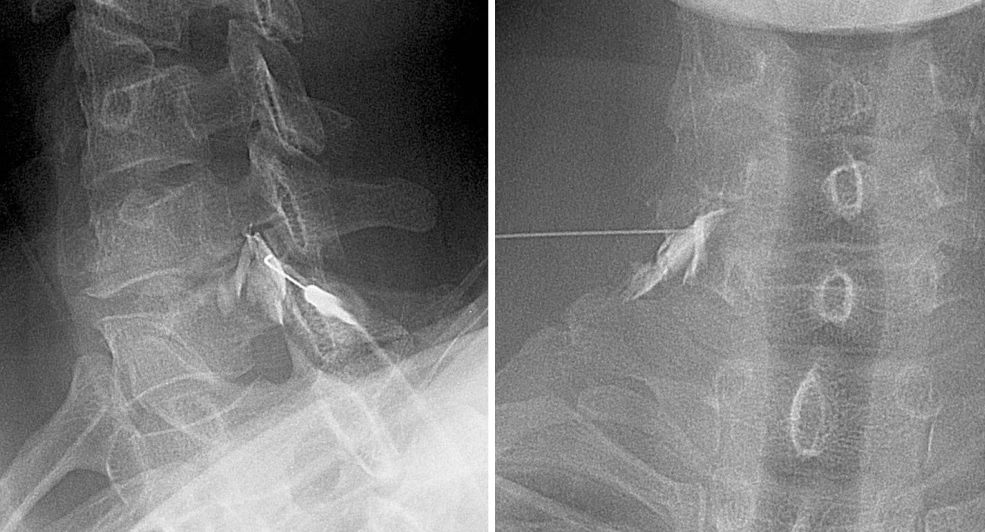

신경차단술: 보통 병원에서 신경차단술(nerve block)이라고 얘기하는데 진단 목적에도 같은 용어를 쓰고 있어 치료용으로는 주사의 삽입 위치에 따라 더 정확히 '경신경공 경막외 주사 (transforaminal epidural injection)'나 '추궁판간 경막외 주사(Interlaminar epidural injection)'등 으로 부르기도 한다 (이준우 & 김성현, 2008).

경신경공 경막외 주사의 X-Ray사진. 경추부 신경공으로 바늘이 삽입되는 것이 보인다. (Source: 이준우 & 김성현, 2008)

탈출된 수핵에서 나오는 염증 유발물질이 통증의 주요 요인이라고 하는데 경막외 주사는 스테로이드 계열의 소염제와 진통제를 병변에 정확히 투여해서 염증을 잡아주는 것이 목적이다. 시술은 90도 각도로 쏴주는 두개의 실시간 X-Ray영상으로 바늘의 위치와 약물의 투입을 정확히 보면서 진행하는데 10분 내외로 간단하고 건강보험 급여대상이다. 내 경우 국내 보험 가입이 안되어 103,540원이 들었다. 약제는 따로 청구되었는데 다 합해야 20만 원 안쪽이다. 건강보험 가입자의 경우 몇만원 정도의 비용이 든다. 참고로 미국의 경우 같은 시술에 보험 적용전 가격으로 $1,000, 즉 120만원 이상이 소요 된다.